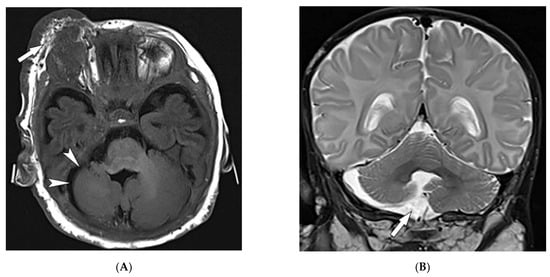

| Behcet’s disease | Oral and genital ulcers Ocular findings Vasculitis CNS lesions | Thickening of the aorta and SVC Bilateral pulmonary artery aneurysms Basal ganglia and brainstem lesions |

| Sturge–Weber syndrome | Port-wine stains Leptomeningeal capillary malformation Glaucoma | Parieto-occipital cortical hemiatrophy Tram-track calcification Calvarial thickening |

| PHACES syndrome | Craniofacial hemangiomas Posterior fossa malformations Cerebrovascular anomalies Eye anomalies | Ipsilateral cerebellar hemisphere dysplasia Major cerebral vessels dysplasia |